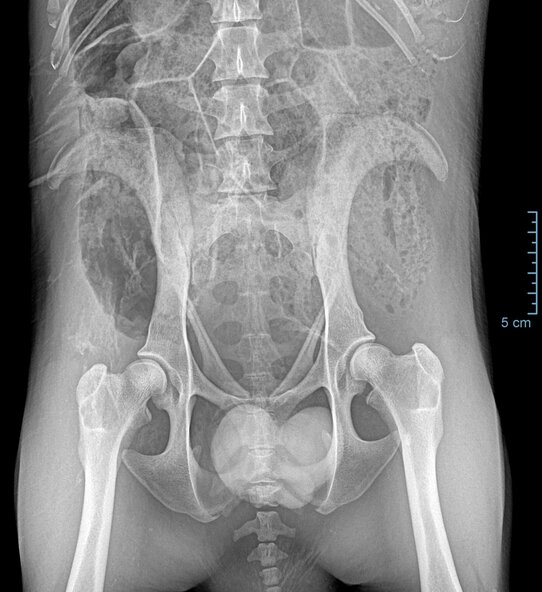

Der Wombat Windemere (geb. 2020) litt im Herbst 2024 an Durchfall, Appetitlosigkeit und Gleichgewichtsstörungen. Nach unauffälligen Laborbefunden erfolgte eine umfangreiche Untersuchung unter Inhalationsnarkose, inklusive Röntgen des Bauches. Die Befunde zeigten eine hohe Gasansammlung im Magen-Darm-Trakt. Die Diagnose: Dysbiose (Störung der Darmflora). Die Futterumstellung weg von Süßkartoffeln hin zu ballaststoffreicherem Bambus sowie Vitamingaben brachten rasch Besserung – Windemere war wenige Tage später wieder wohlauf und durfte zurück zu seiner Partnerin Wendy ins Gehege.